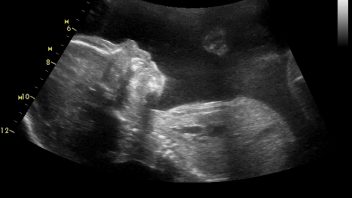

Lucinka právě prožívá 29. týden těhotenství. Jak roste její miminko v bříšku a co se děje s ní?